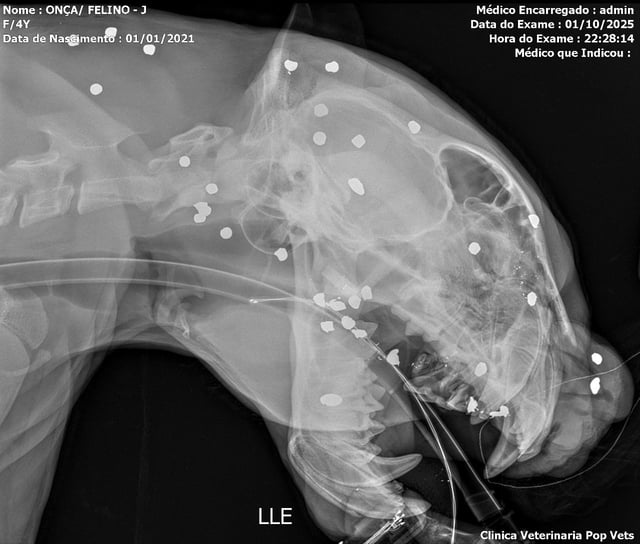

X-Rays Show 30 Pellets in Jaguar Rescued From Rio Negro

• Imaging revealed more than 30 shotgun fragments across the face, head and neck, along with broken teeth and visible head wounds.

• A felid biologist said the spread of pellets indicates a distant discharge, possibly intended to drive the animal away.